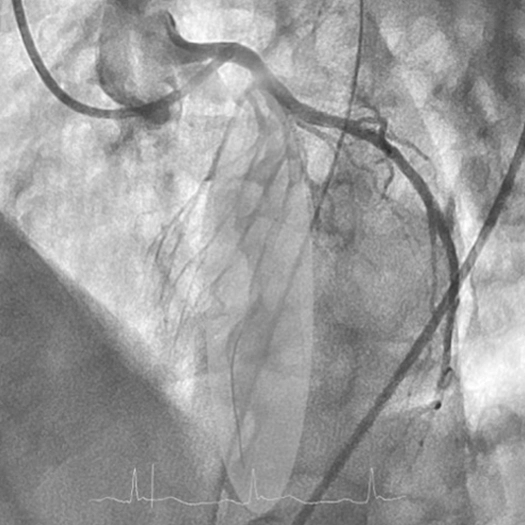

Portion of the LAD territory highlighted. Seen again is the interventional wire for reference. Portion of the LAD territory highlighted. Seen again is the interventional wire for reference.

Photo 2: Portion of the LAD territory highlighted. Seen again is the interventional wire for reference.